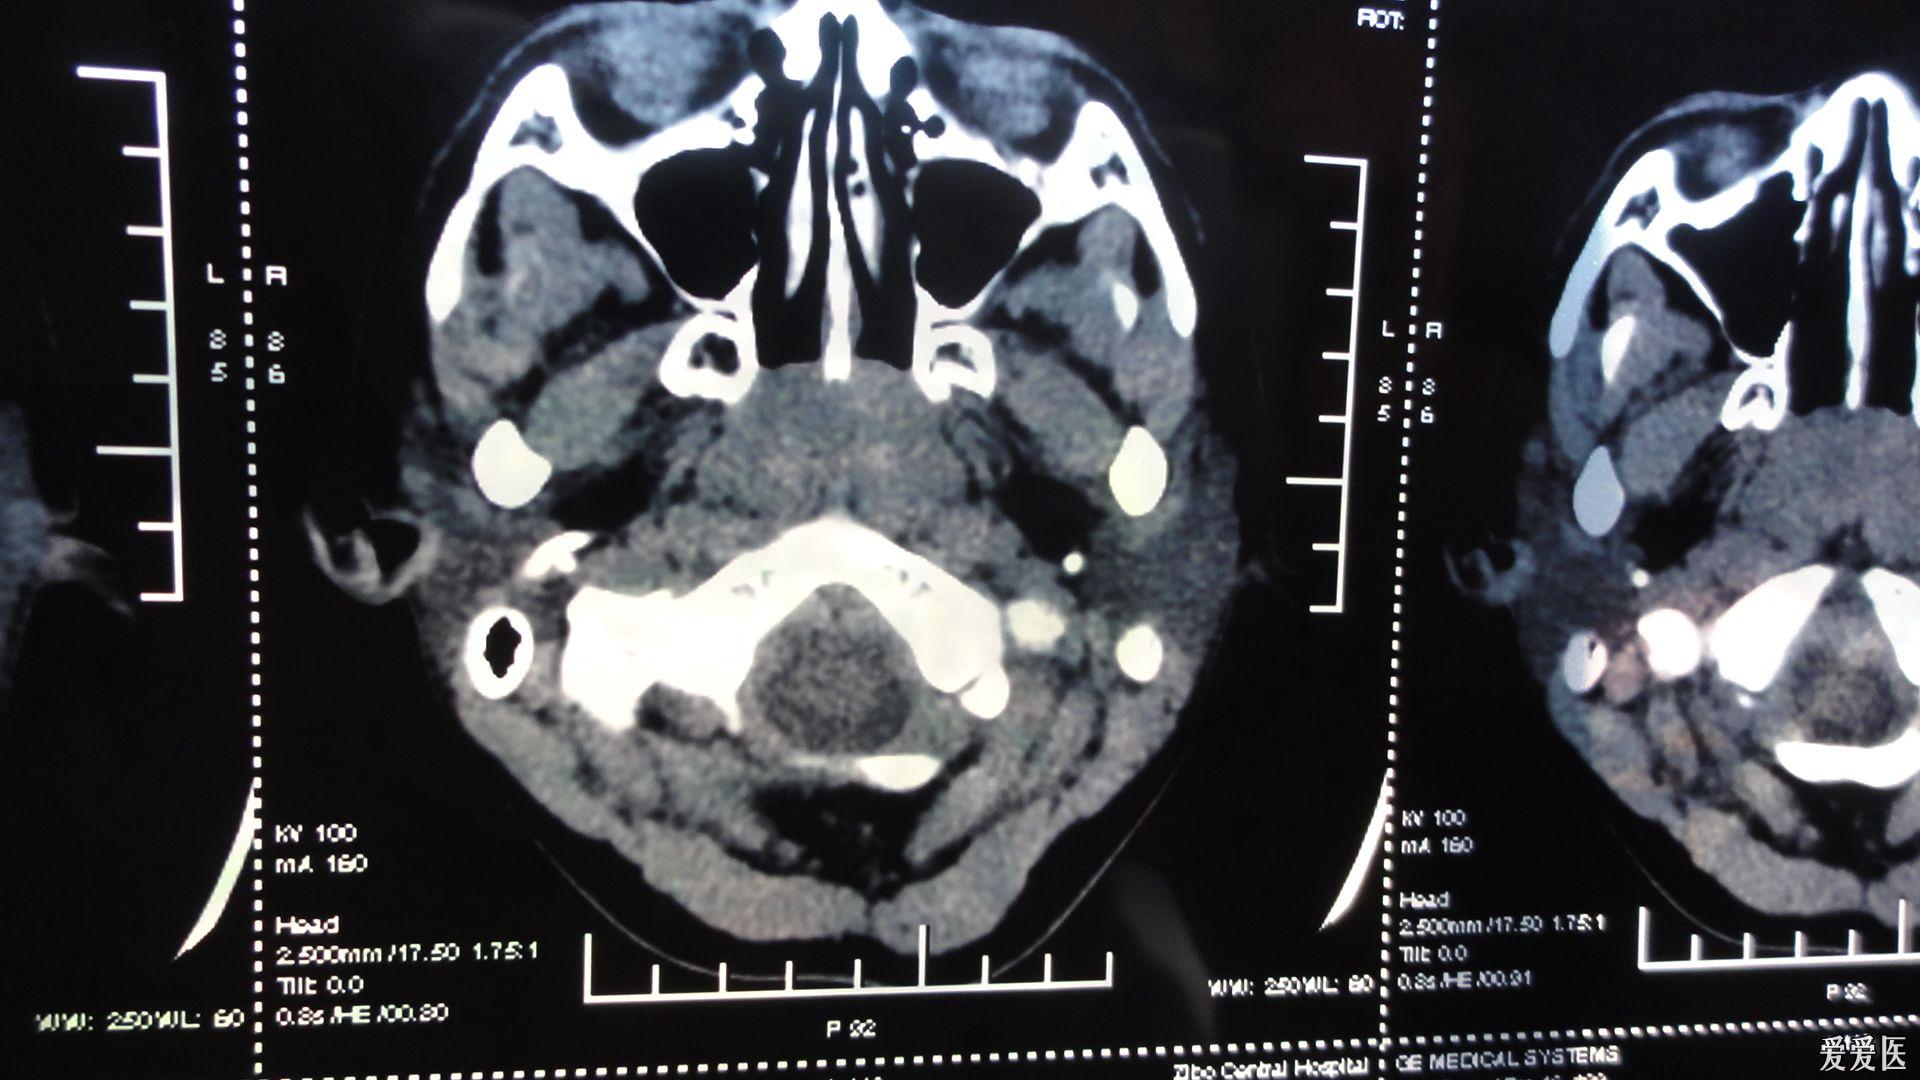

儿童腺样体肥大丨识别与诊治,x线测量方法_增殖腺

腺样体肥大是一种常见的儿童疾病,也称为咽扁桃体肥大或增殖体肥